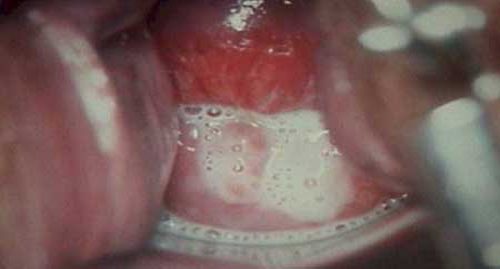

В зависимости от формы трихомоноза, женщину может начать беспокоить зуд, жжение, ощущение тяжести и боли в области паха. Болевые ощущения усиливаются, становятся острыми и режущими в процессе мочеиспускания. Гинеколог при осмотре больной может наблюдать гиперемию слизистой оболочки влагалища и обильные пенистые выделения. Гиперемия не проявляется при хронической форме заболевания.

7. Гиперемии слизистой оболочки половых органов со следами точечных кровотечений.